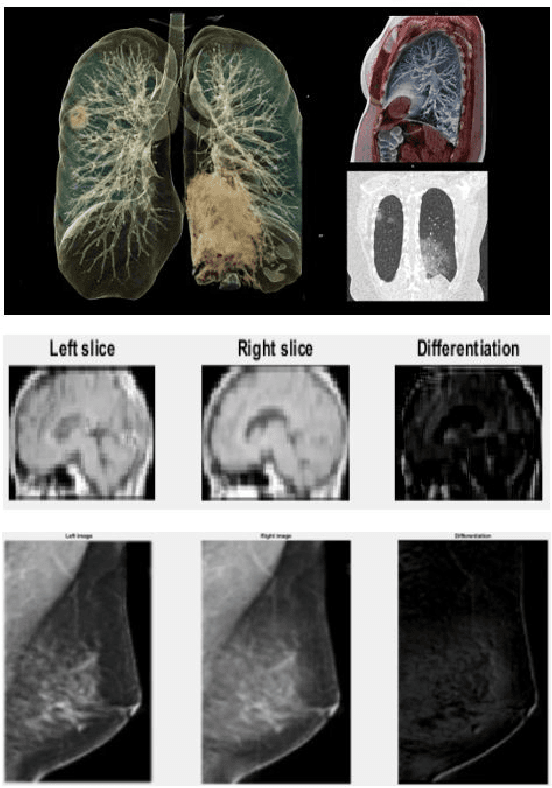

Abstract:The paper proposes a novel hybrid discovery Radiomics framework that simultaneously integrates temporal and spatial features extracted from non-thin chest Computed Tomography (CT) slices to predict Lung Adenocarcinoma (LUAC) malignancy with minimum expert involvement. Lung cancer is the leading cause of mortality from cancer worldwide and has various histologic types, among which LUAC has recently been the most prevalent. LUACs are classified as pre-invasive, minimally invasive, and invasive adenocarcinomas. Timely and accurate knowledge of the lung nodules malignancy leads to a proper treatment plan and reduces the risk of unnecessary or late surgeries. Currently, chest CT scan is the primary imaging modality to assess and predict the invasiveness of LUACs. However, the radiologists' analysis based on CT images is subjective and suffers from a low accuracy compared to the ground truth pathological reviews provided after surgical resections. The proposed hybrid framework, referred to as the CAET-SWin, consists of two parallel paths: (i) The Convolutional Auto-Encoder (CAE) Transformer path that extracts and captures informative features related to inter-slice relations via a modified Transformer architecture, and; (ii) The Shifted Window (SWin) Transformer path, which is a hierarchical vision transformer that extracts nodules' related spatial features from a volumetric CT scan. Extracted temporal (from the CAET-path) and spatial (from the Swin path) are then fused through a fusion path to classify LUACs. Experimental results on our in-house dataset of 114 pathologically proven Sub-Solid Nodules (SSNs) demonstrate that the CAET-SWin significantly improves reliability of the invasiveness prediction task while achieving an accuracy of 82.65%, sensitivity of 83.66%, and specificity of 81.66% using 10-fold cross-validation.

Abstract:Lung cancer is the leading cause of mortality from cancer worldwide and has various histologic types, among which Lung Adenocarcinoma (LAUC) has recently been the most prevalent. Lung adenocarcinomas are classified as pre-invasive, minimally invasive, and invasive adenocarcinomas. Timely and accurate knowledge of the invasiveness of lung nodules leads to a proper treatment plan and reduces the risk of unnecessary or late surgeries. Currently, the primary imaging modality to assess and predict the invasiveness of LAUCs is the chest CT. The results based on CT images, however, are subjective and suffer from a low accuracy compared to the ground truth pathological reviews provided after surgical resections. In this paper, a predictive transformer-based framework, referred to as the "CAE-Transformer", is developed to classify LAUCs. The CAE-Transformer utilizes a Convolutional Auto-Encoder (CAE) to automatically extract informative features from CT slices, which are then fed to a modified transformer model to capture global inter-slice relations. Experimental results on our in-house dataset of 114 pathologically proven Sub-Solid Nodules (SSNs) demonstrate the superiority of the CAE-Transformer over the histogram/radiomics-based models and its deep learning-based counterparts, achieving an accuracy of 87.73%, sensitivity of 88.67%, specificity of 86.33%, and AUC of 0.913, using a 10-fold cross-validation.